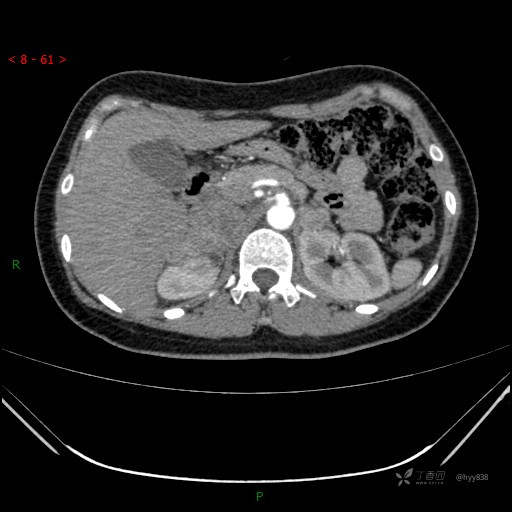

静脉期